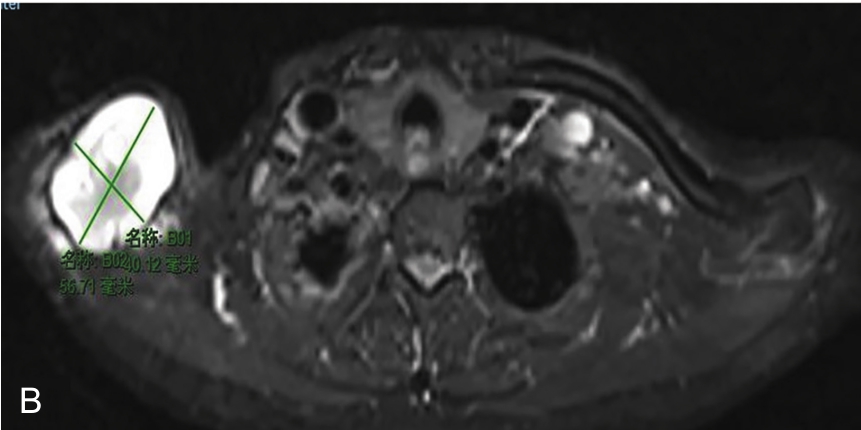

▲ 图2-1-12 超声引导下右侧肩关节周围滑膜囊肿穿刺治疗

A~B.患者肩关节MRI,星号及测量键:滑膜囊肿